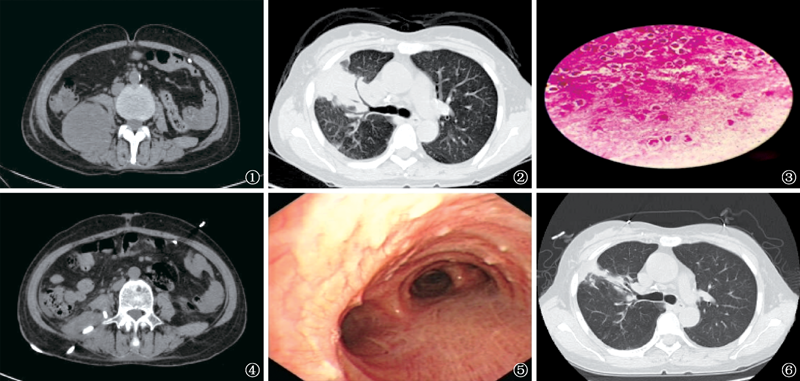

图1 患者,女,56岁。 2019年10月24日,腹部CT扫描示右侧腰3、4锥体水平右缘囊性病变,大小7.0cm×5.3cm,局部与背部肌肉分界不清晰 图2 2019年10月25日,胸部CT扫描示右肺斑片状密度增高影,边界欠清晰,纵隔淋巴结钙化,双侧少量胸腔积液 图3 2019年10月25日腋下脓肿穿刺脓液涂片示:弱抗酸染色阳性,杆菌,细长,呈分枝状(油镜10× 100) 图4 2019年10月29日腹部增强CT扫描示右髂腰部低密度影(内见引流管),体积缩小,边缘明显强化 图5 2019年11月8日气管镜检查,主支气管内广泛结节样突起,左右主支气管及各叶支气管黏膜光滑,管腔通畅 图6 2019年11月9日胸部CT扫描示两肺斑点、斑条状高密度影,右上肺柱状支气管扩张影,病灶缩小